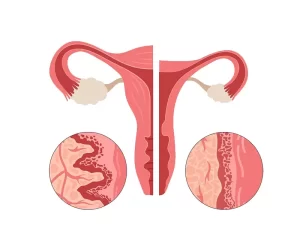

فیبروم رحم

فیبروم ها تومورهای غیرسرطانی و خوش خیم هستند که در لایه های عضلانی رحم رشد می کنند. فیبروم شایع ترین تومور لگنی در ...